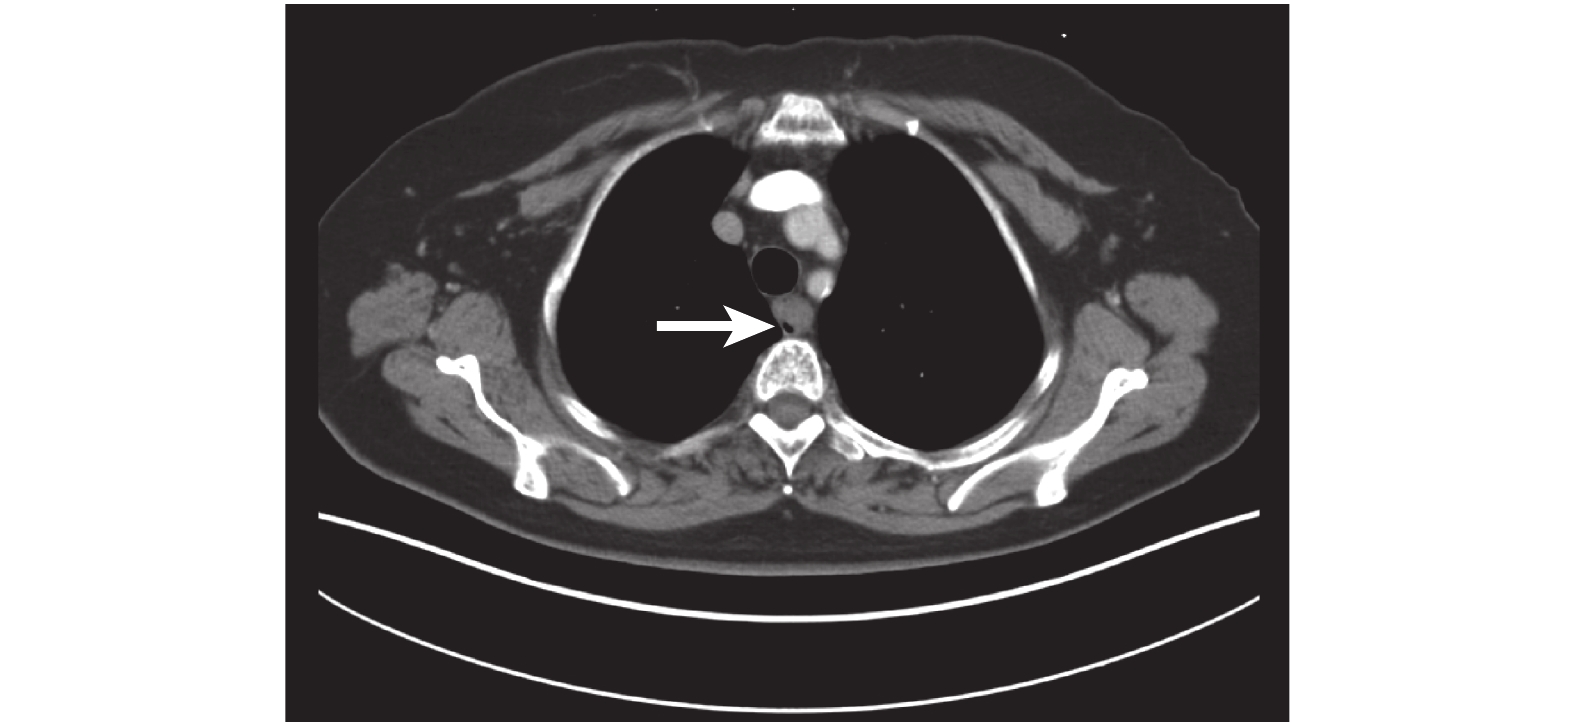

病例 3:患者,女,72 歲,患者進食梗阻感 1 個月為主訴入院治療,外院胃鏡示:距門齒 20 cm,占位 5 mm×4 mm,PET-CT:食管腔內占位,CT 顯示食管上中段局部管壁不規則增厚,最大層面 2.3 mm×2.0 mm,侵及長度為 4.5 cm,局部管腔狹窄,狹窄以上食管輕度擴張,CT 值為 29~47 Hu,結論為食管上中段癌可能(圖 3)。食管鏡顯示:距門齒 20~23 cm,見左壁占位性病變,傘形,窄蒂,診斷為食管占位性病變(圖 4)。吞鋇餐見食管胸中段長約 1~2 個椎體充盈缺損,診斷為食管胸中段癌。患者于全身麻醉下行食管腫瘤套切術,術后 3 個月隨訪,生活質量良好,術后 2 年隨訪患者腫瘤復發死亡。